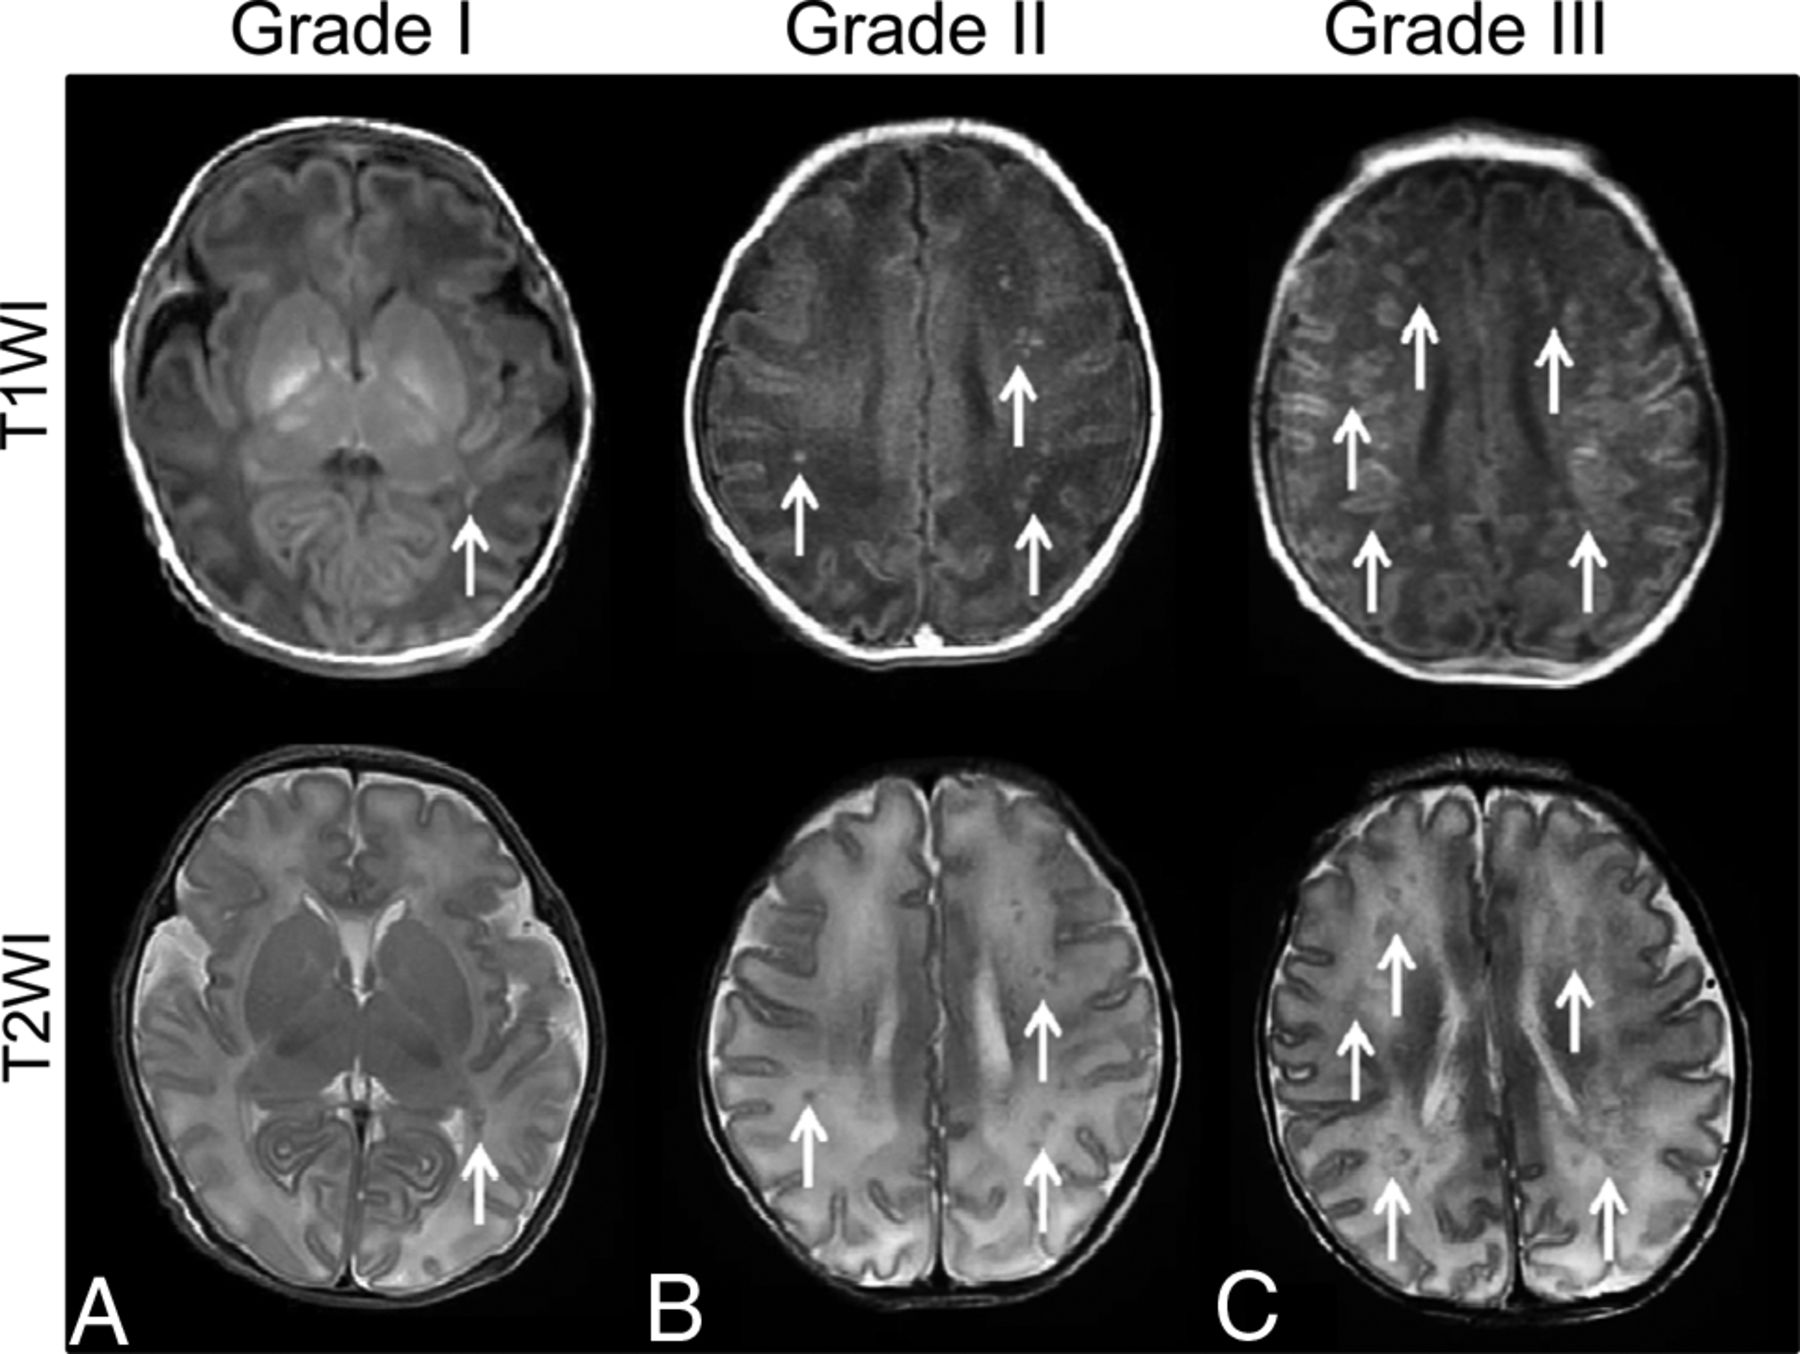

PWMLs were mainly located in the white matter adjacent to lateral ventricles, especially the regions lateral to the trigone, posterior horns, and the centrum semiovale and/or corona radiata (Fig 1). The intrarater and interrater correlation coefficients for the lesion number counting were 0.994 (95% confidence interval, 0.989∼0.997) and 0.974 (95% confidence interval, 0. 948∼0. 987), respectively. For grades I and II, most of the lesions were located in the posterior region (Table 3). For grade III, more lesions were located in the central and posterior regions than in the anterior region (Table 3).

The appearances of 3 PWML grades (A, grade I; B, grade II; C, grade III) on T1WI and T2WI.

The extent of microstructural alterations was different across PWML grades. There were no significant changes in grades I and II compared with controls (P ≥ .05). For neonates with PWML grade III, reduced FA, increased AD, and increased RD were observed in the centrum semiovale and/or corona radiata, white matter near the trigone of the lateral ventricles, SCC, and OR (Fig 2). These regions were near PWML sites seen on T1WI and T2WI (Fig 1). Reduced FA, unchanged AD, and increased RD were observed in regions distant from the lesion sites, including the CST in the posterior limb of the internal capsule, more extensive areas in the OR, and the central part of the SCC, GCC, IFO, and the external capsule (Fig 2).